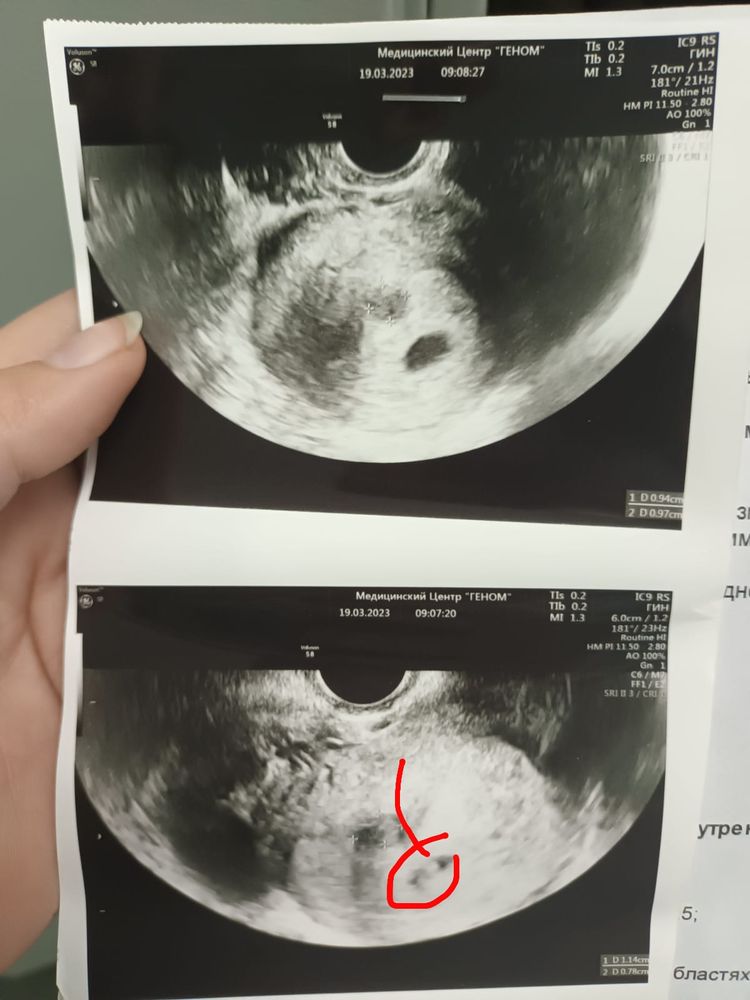

Изображение Это 18 ДПП Изображение Это 25 дпп На 18 мне просто моя врач посмотрела прикрепился ли)) всего лишь точечка. А уже на 25 дпп у меня было назначено узи и мне сразу сказали что сердечко забилось))) подождите ещё чуть чуть))) главное не переживайте!))